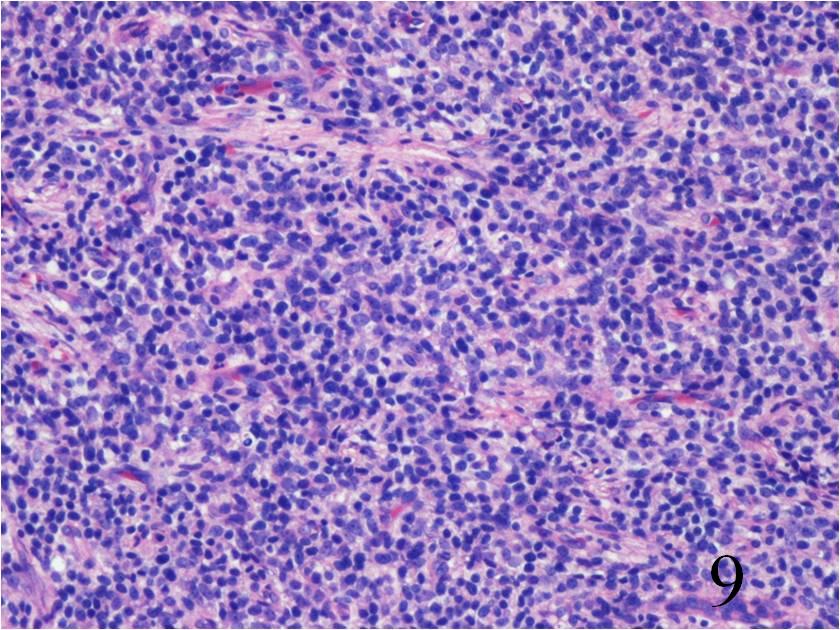

Fig. 9

Fig. 10

Fig. 9-10 Microscopic: Low power (Fig. 9) and high power (Fig. 10) views of an Extraskeletal Ewing Sarcoma shows a monotonous Collectionb of small round blue cells. The cells have large nuclei and minimal cytoplasm.